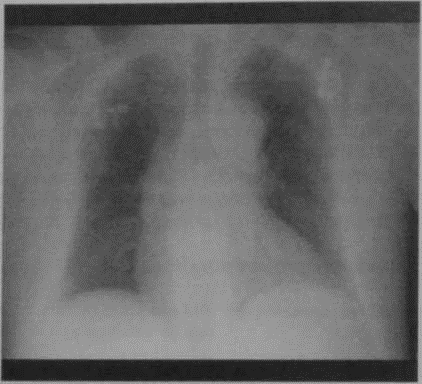

Что покажет рентген грудной клетки

- У пациентов с компенсированной СН часто без патологии

- Может определяться увеличение контуров сердца

- Хронический венозный застой в легочных сосудах

- Застойный фиброз легких из-за рекуррентной декомпенсации СН.

Постинфарктныйкардиосклероз. На обзорнойрентгенографии грудной клетки в переднезадней проекцииопределяется кардиомегалияс декомпенсированной левожелудочковой СН, расширениемЛЖ и хроническим венознымзастоем в сосудах легких.